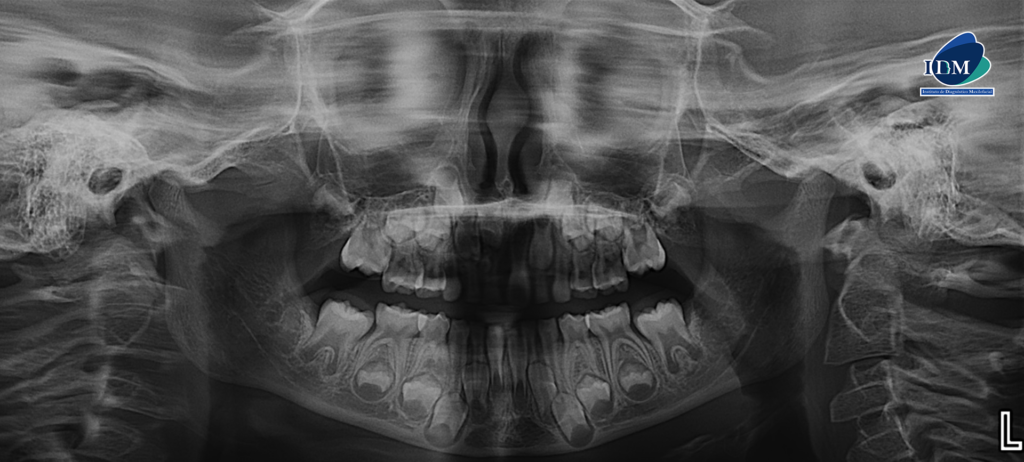

En la radiografía panorámica (Figura 1), se aprecia imagen radiopaca de densidad dentaria, de limites definidos circunscrita con un halo radiolúcido, proyectado en tercio medio y apical de pieza 52-51, observándose en el interior múltiples dentículos.

A la evaluación de la tomografía volumétrica (CBCT) en los cortes axiales (Figura 2) y transaxiales(Figura 3), se aprecia múltiples dentículos circunscrito de un halo hipodenso, localizada en palatino del tercio apical y medio de piezas 52-51, que ocasiona el desplazamiento de la pieza 11 hacia cefálico y adelgazamiento de la tabla ósea palatina En las reconstrucciones 3D se representa odontoma compuesto. (Figura 4).

CORTES AXIALES